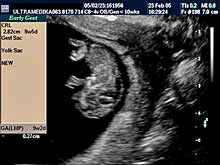

C) III trimestar trudnoće

od 24. do 40. nedelje trudnoće

Indikacija za ultrazvučni pregled:

- Procena funkcije bubrega, organa abdomena, srca i cirkulacije likvora

u mozgu.

Napomena: Na svakom pregledu do kraja trudnoće.

- Stalna procena ehostrukture organa ploda i njegov ukupni porast.

Napomena: Kod "hiperehogenih bubrega" procena renalnih aretrija CPD.

Stalna procena volumena pluća, želudca i veličine creva.

- Procena bolesti histiogeneze mozga ploda od 26 nedelje gestacije.

Napomena: Procena moždane cirkulacije Broadband - CD i CPA i/ili 3DCPA.

- Procena izostanka treće faze embriogeneze mozga

OD 26 NEDELJE DO KRAJA

TRUDNOĆE.

- U slučaju zastoja porasta ploda procena redistribucije krvotoka i

određivanja termina porođaja.

Napomena: Tačnost je zasnovana na

primeni Broadband Color Dopplera i Color Power Dopplera.

- Procena posteljice i protoka pupčanika, kao i njegov tok i položaj.

Napomena: mogućnost pogrešnog položaja pupčanika na posteljici,

njegovo prednjačenje u porođaju, ili njegov neadekvatan položaj oko

dela tela ploda, ili formiranje čvora ili zapušenje, su krucijalna

informacija u toku pregleda do tada normalne trudnoće.

Napomena:

U III trimestru pregled trudnoće zbog velikog broja

indikacija treba nastaviti u 4 nedeljnim intervalima. Nekad se donosi

odluka o ranijem terminu porođaja, hitnom carskom rezu, a izuzetno

retko o prekidu trudnoće na osnovu podataka dobijenih u toku redovne

ultrazvučne kontrole trudnoće u III trimestru.